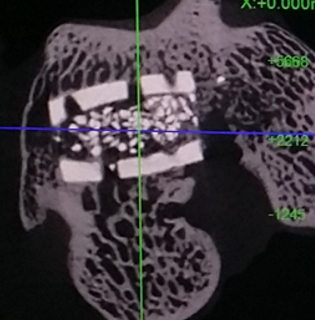

대구 첨복 마이크로 CT촬영을 위해 미팅을 잡고 교수님과 방문하여 회의를 하였습니다. 언제 검체를 들고 방문하겠다는 약속을 잡고, 실제로 촬영을 마치고 돌아왔습니다. 이 실험을 도와주신 분은 위한 첨복 실험동물센터 김동규 박사님이었습니다. 마이크로 CT촬영을 진행하면서 박사님께 “이 실험이 제 학위 논문을 위한 실험”이라고 말씀드리니 저에게 “박사가 되기 위해서 많이 노력하시는 것 같다”라고 격려 말씀을 해주셨던 기억이 있습니다. 촬영 후에 영상의학적 분석을 진행하면서 박사님을 귀찮게 하였던 기억이 납니다. (사진 3)

phd3.png 사진 3. 첨단 과학의 눈: 마이크로 CT가 포착한 골 형성의 순간. 골 형성의 비밀을 캐내는 중요한 단서입니다.